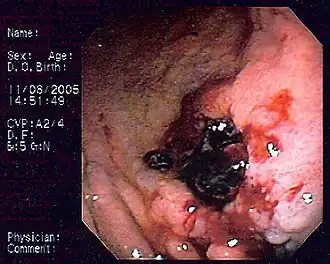

MALT-лимфома желудка | |